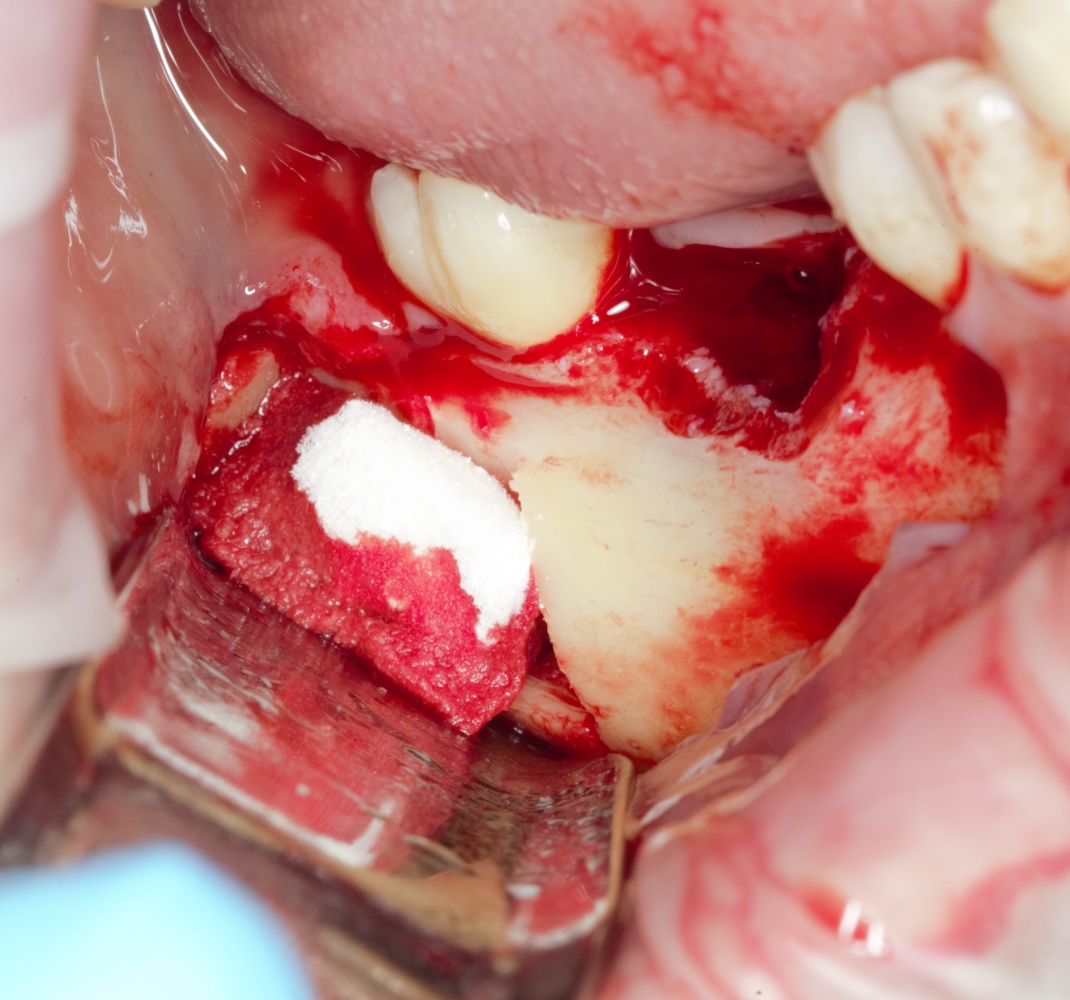

Забор костного фрагмента проводится с наружной косой линии с помощью ультразвукового пьезохирургического инструмента. Ничего сверхнового и супернеобычного тут нет, совершенно стандартная методика. С той лишь разницей, что молоток для этого используют только фашисты и только в гестапо использовать не нужно, всё делается усилием и ловкостью рук.

Нюансы начинаются с обработки принимающего ложа. Да-да, уважаемые друзья, одна из причин некроза блоков, их чрезмерной атрофии и прочих проблем — в отсутствии обработки принимающего ложа. Некоторые делают дырки, но правильнее и эффективнее поступить так:

то есть, просто снять слой кортикальной пластинки с участка, к которому будет фиксироваться костный блок. Почему? Читайте здесь>>.

Вторая особенность — мы не адаптируем и не обрабатываем костный блок invitro, а фиксируем его так, как есть:

после чего обрабатываем — доводим до окончательной формы альвеолярного гребня: